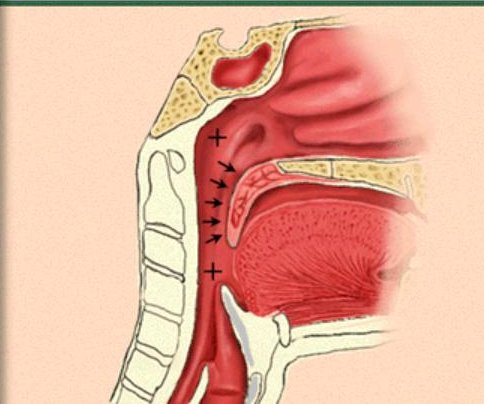

The positive pressure splints the airway open preventing collapse.

Surgical revision of the uvula, tonsils, soft palate, and soft tissues of the oropharynx may provide significant relief of obstruction in selected patients. - Laser - assisted uvulopalatoplasty (LAUP) Surgical revision of the uvula, tonsils and soft palate, using laser technology may also provide significant relief of obstruction in these patients.